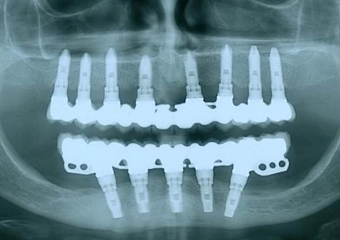

Raio X inicial